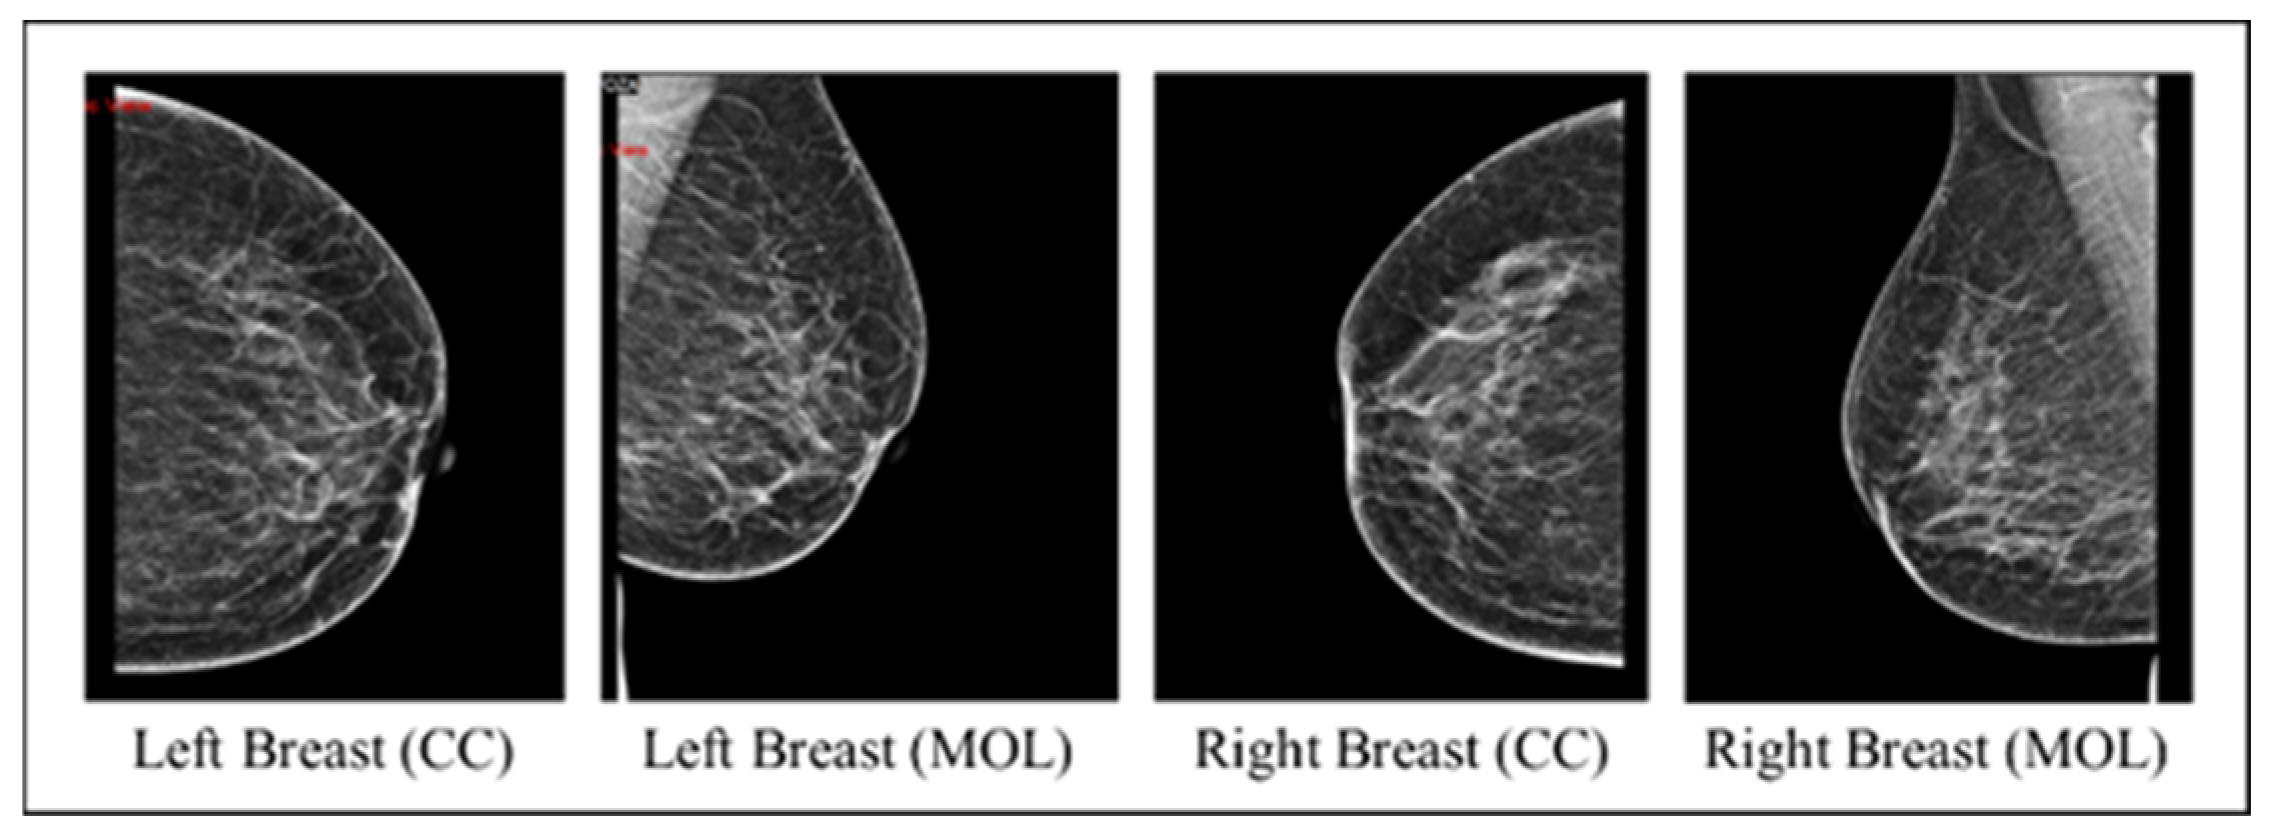

- Checking that each record includes MLO and CC views for both breasts.

- Uncleaned images: the model processes images containing text, with four mammograms for each patient, covering two views per breast side.

- Cleaned images: the same model is then applied to images devoid of text, also featuring four mammograms per patient and two views per breast side.

- The outperforming scenario between the uncleaned and cleaned images is rerun using only two images from the two views of the affected breast side.